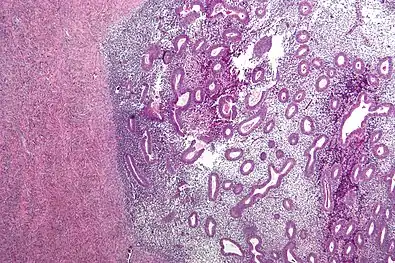

Endometriosis, abdominal wall

Micrograph showing endometriosis (right) and ovarian stroma (left).

Histopathology

For a histopathological diagnosis, at least two of the following three criteria should be present:[88]

- Endometrial type stroma

- Endometrial epithelium with glands

- Evidence of chronic hemorrhage, mainly hemosiderin deposits

Immunohistochemistry has been found to be useful in diagnosing endometriosis as stromal cells have a peculiar surface antigen, CD10, thus allowing the pathologist go straight to a staining area and hence confirm the presence of stromal cells and sometimes glandular tissue is thus identified that was missed on routine H&E staining.[89]